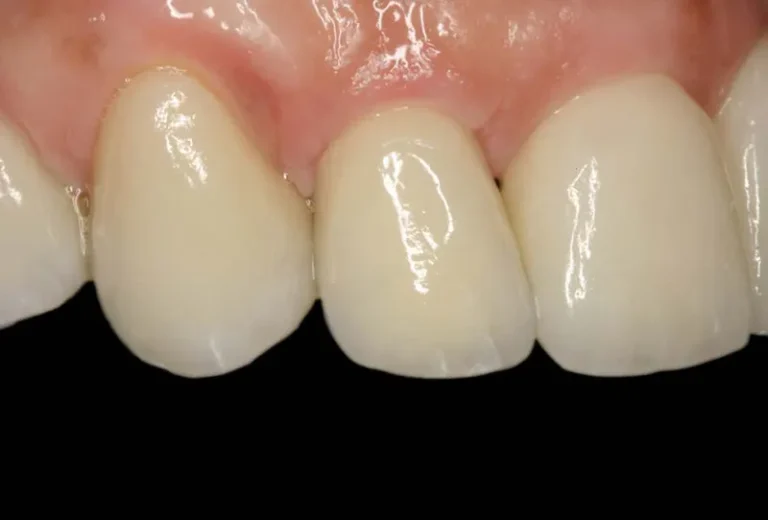

Las diferencias entre implante dental y puente dental son fundamentales para elegir el tratamiento más adecuado. El implante dental consiste en un tornillo de titanio que se inserta en el hueso maxilar, reemplazando la raíz del diente perdido, mientras que el puente dental se apoya en los dientes adyacentes para sostener la prótesis. Aunque ambas…